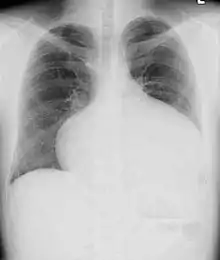

Abnormal chest X-ray as seen in a patient of atrial septal defect

Most individuals with a significant ASD are diagnosed in utero or in early childhood with the use of ultrasonography or auscultation of the heart sounds during physical examination. Some individuals with an ASD have surgical correction of their ASD during childhood. The development of signs and symptoms due to an ASD are related to the size of the intracardiac shunt. Individuals with a larger shunt tend to present with symptoms at a younger age.

Adults with an uncorrected ASD present with symptoms of dyspnea on exertion (shortness of breath with minimal exercise), congestive heart failure, or cerebrovascular accident (stroke). They may be noted on routine testing to have an abnormal chest X-ray or an abnormal ECG and may have atrial fibrillation. If the ASD causes a left-to-right shunt, the pulmonary vasculature in both lungs may appear dilated on chest X-ray, due to the increase in pulmonary blood flow.[33]